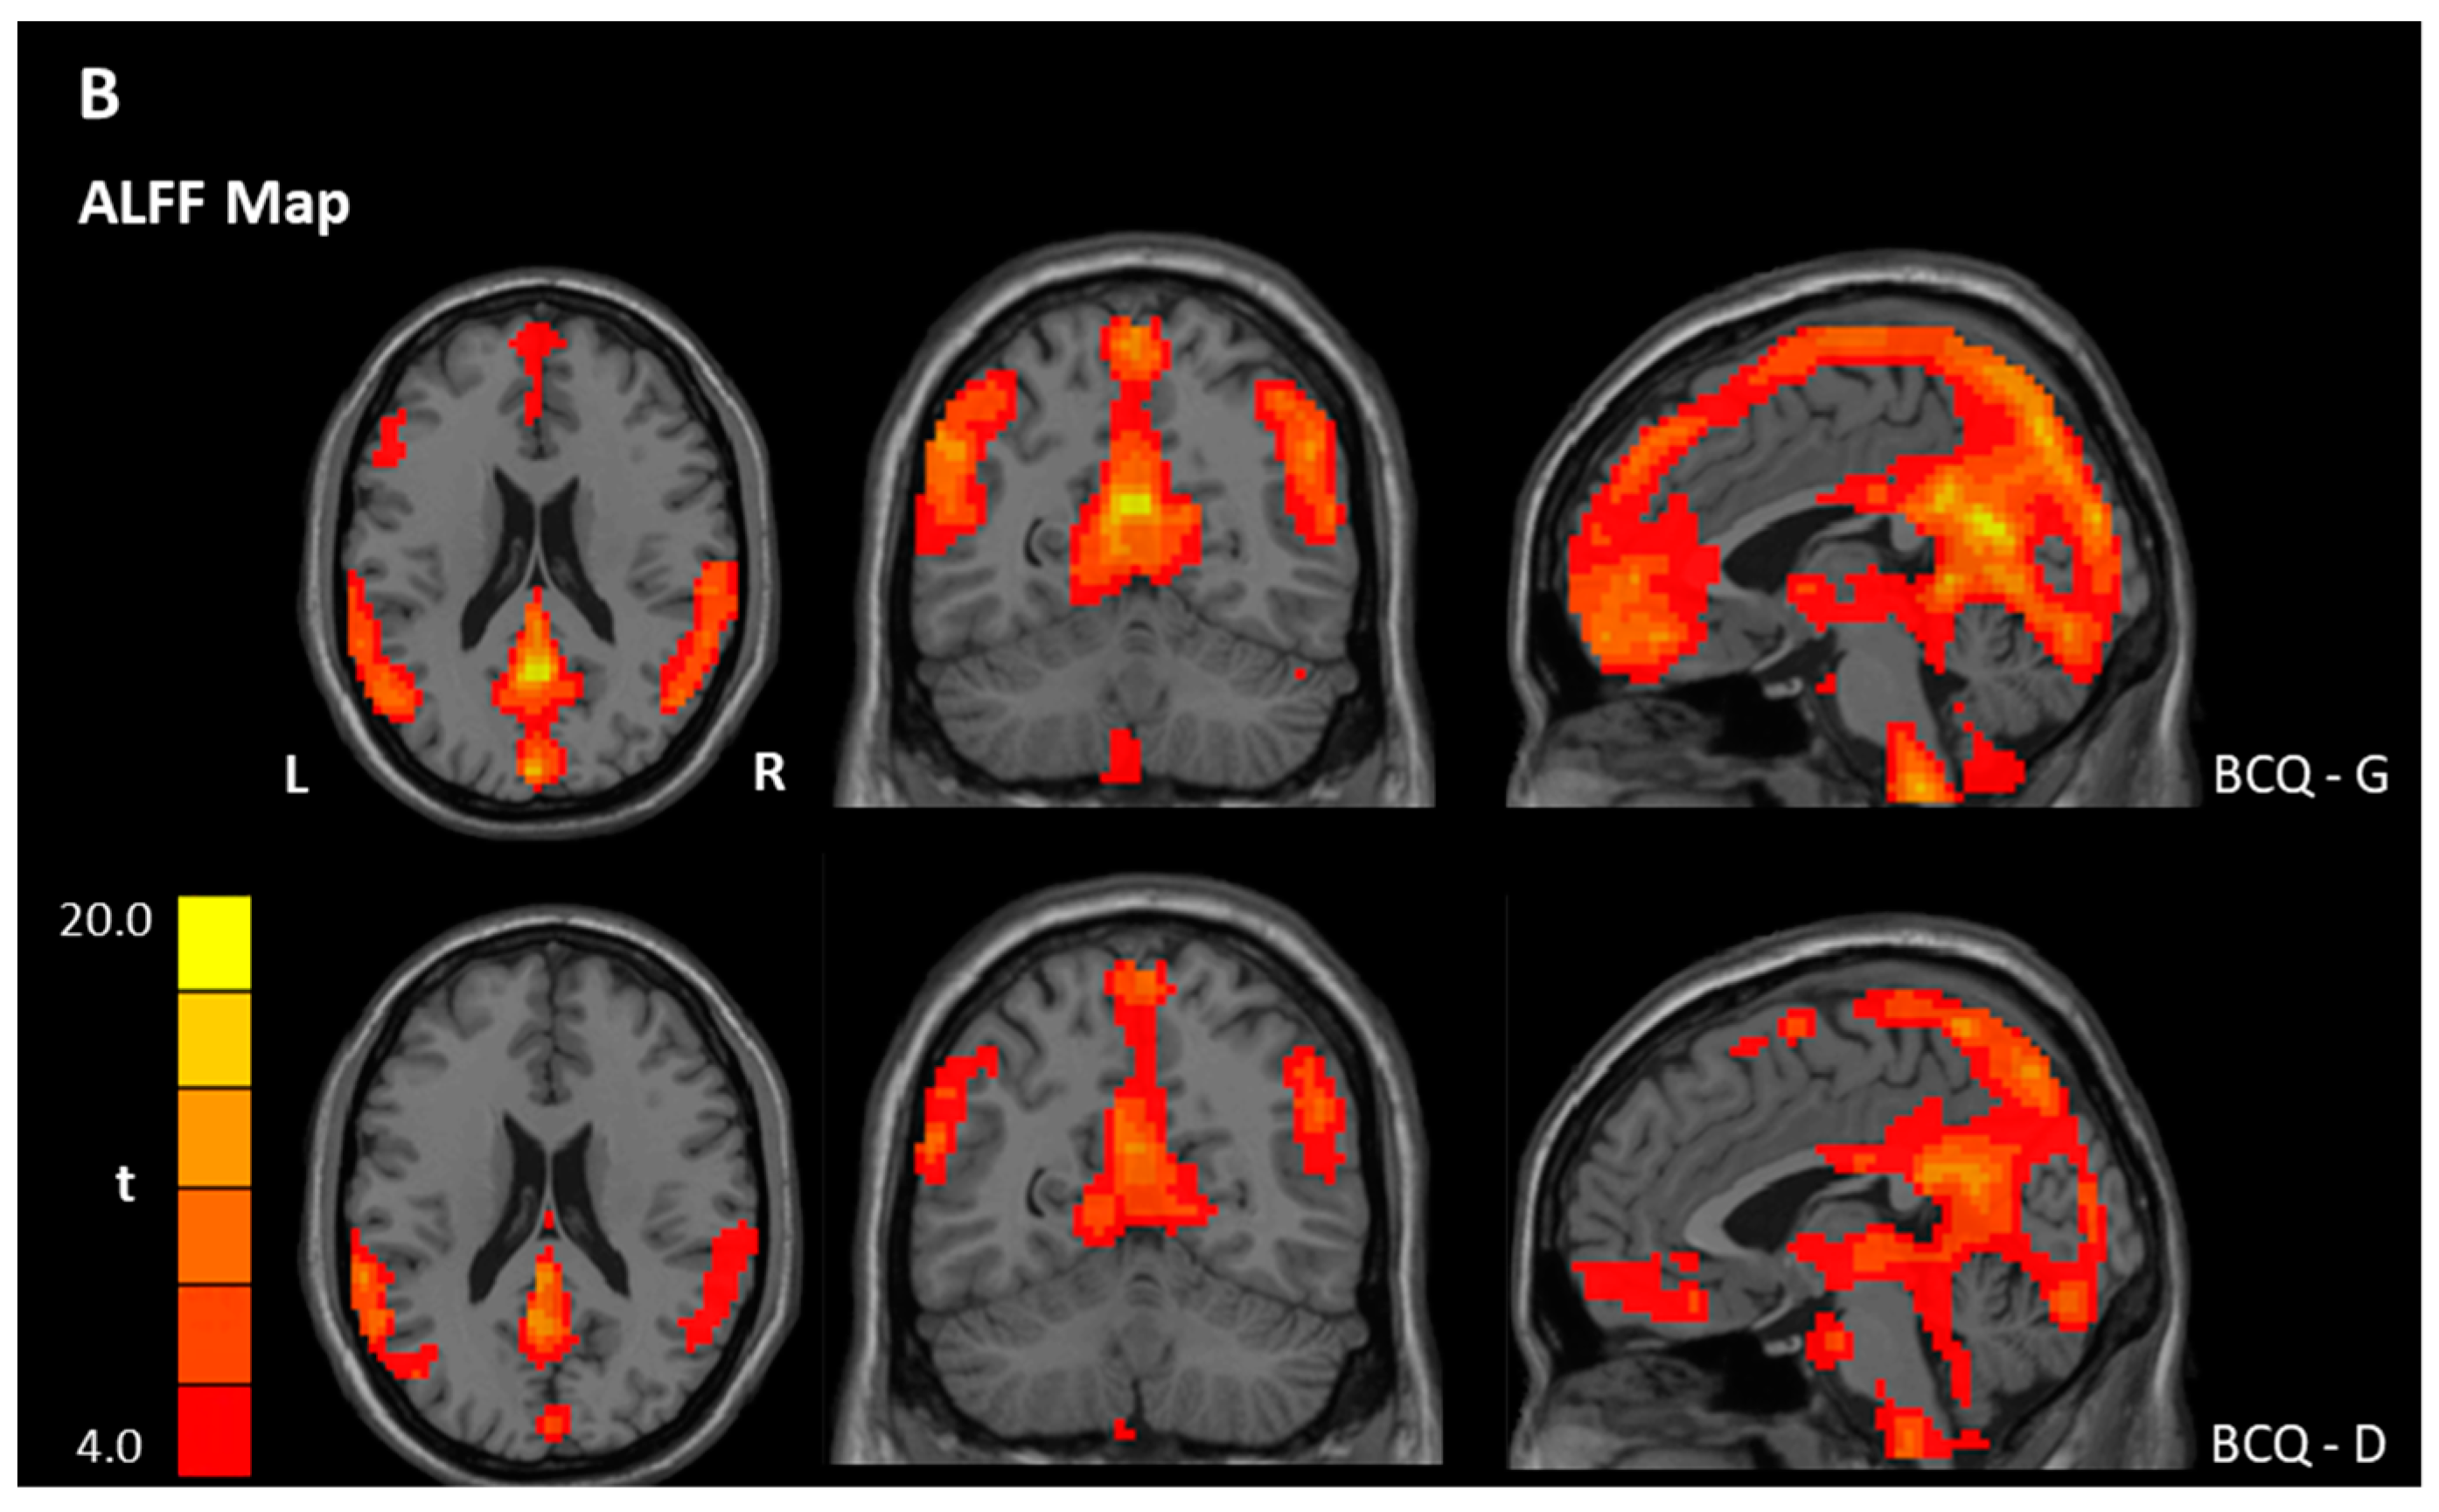

3.3. ReHo and ALFF Analyses

| ALFF | |||||||

| Within-group ** | |||||||

| BCQ-Gentleness | |||||||

| Gentleness > 0 | PCC | 23 | 11639 | 17.34 | −3 | −54 | 21 |

| Gentleness < 0 | NS | ||||||

| BCQ-Deficiency | |||||||

| Deficiency > 0 | OFC, Left | 11 | 161 | 6.79 | −33 | 33 | −18 |

| Deficiency < 0 | Precentral gyrus, Left | 6 | 29,955 | 52.63 | −18 | −18 | 54 |

| Between-group * | |||||||

| Gentleness > Deficiency | NS | ||||||

| Gentleness < Deficiency | Pons/Cerebellum, Left | 85 | −3.86 | −12 | −36 | −54 | |